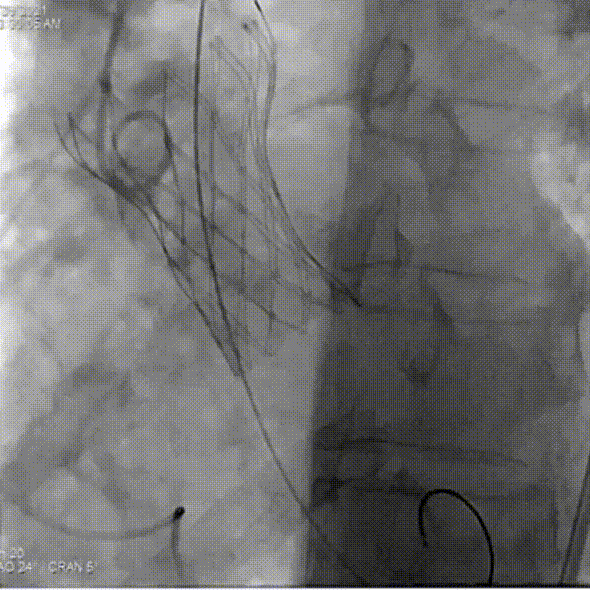

主动脉根部造影

球囊预扩

第一次尝试释放

位置偏深回收调整,进行第二次释放

瓣膜流入端被压缩有上跳风险,再一次进行回收

第三次释放

人工瓣有相应折叠,全部回收撤出体外

更换后瓣膜再一次进行释放

部分回收进行位置的微调整

完全释放后,主动脉根部造影